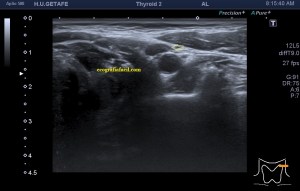

Era un nódulo hiperecogénico en el contexto de la tiroiditis en el estudio de una ecografía tiroidea.

Te enseño las imágenes, típicas de una exploración tiroidea de protocolo con semiología de tiroiditis.

De la imagen 1 a 7 el protocolo habitual, el estudio particular del nódulo con medidas y aplicación del doppler demuestra el aspecto típico del Caballero Blanco.

De la 8 a la 11 estudio con Doppler.

La imagen 12 y 13 están adquiridas con una sonda de 18 Mhz.

El Caballero blanco, recibe el nombre debido a su semiología hiperecogénica, homogénea y solitaria circunscrito en la patología referida con anterioridad, puede aparecer en esta patología de forma benigna o degenerar en otro tipo de patología a formas malignas como el linfoma tiroideo.